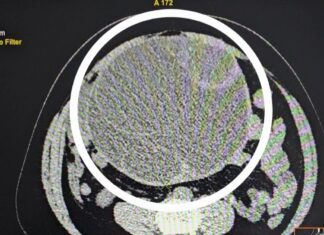

У молодой жительницы Заречного удалили гигантскую опухоль

Хирурги ФГБУЗ МСЧ №59 ФМБА России города Заречный Пензенской области удалили гигантскую опухоль брюшной полости у молодой девушки.

Девушка обратилась в приемный покой с жалобами на сильную боль в животе. Во время осмотра в животе...